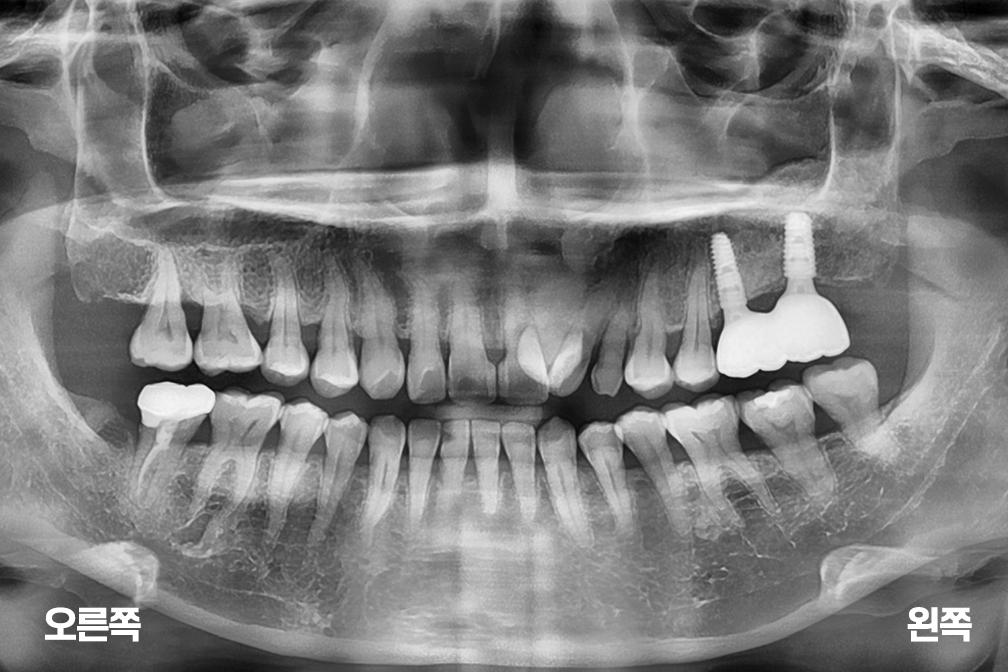

임플란트 상악동 거상술 및 왼쪽 윗 어금니 두개 임플란트 수술

상악동거상술 + 임플란트 수술

위 전후사진은 이미지사진으로 실제 눈으로 보는 것과는 다를 수 있으며, 환자의 치아상태과 방법에 따라 치료결과가 다를수 있습니다.